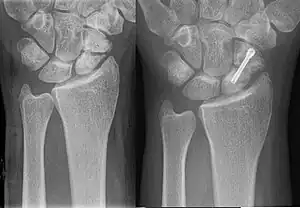

| An X-ray showing a fracture through the waist of the scaphoid | |

A subtle scaphoid fracture

A more obvious scaphoid fracture on a scaphoid view X ray